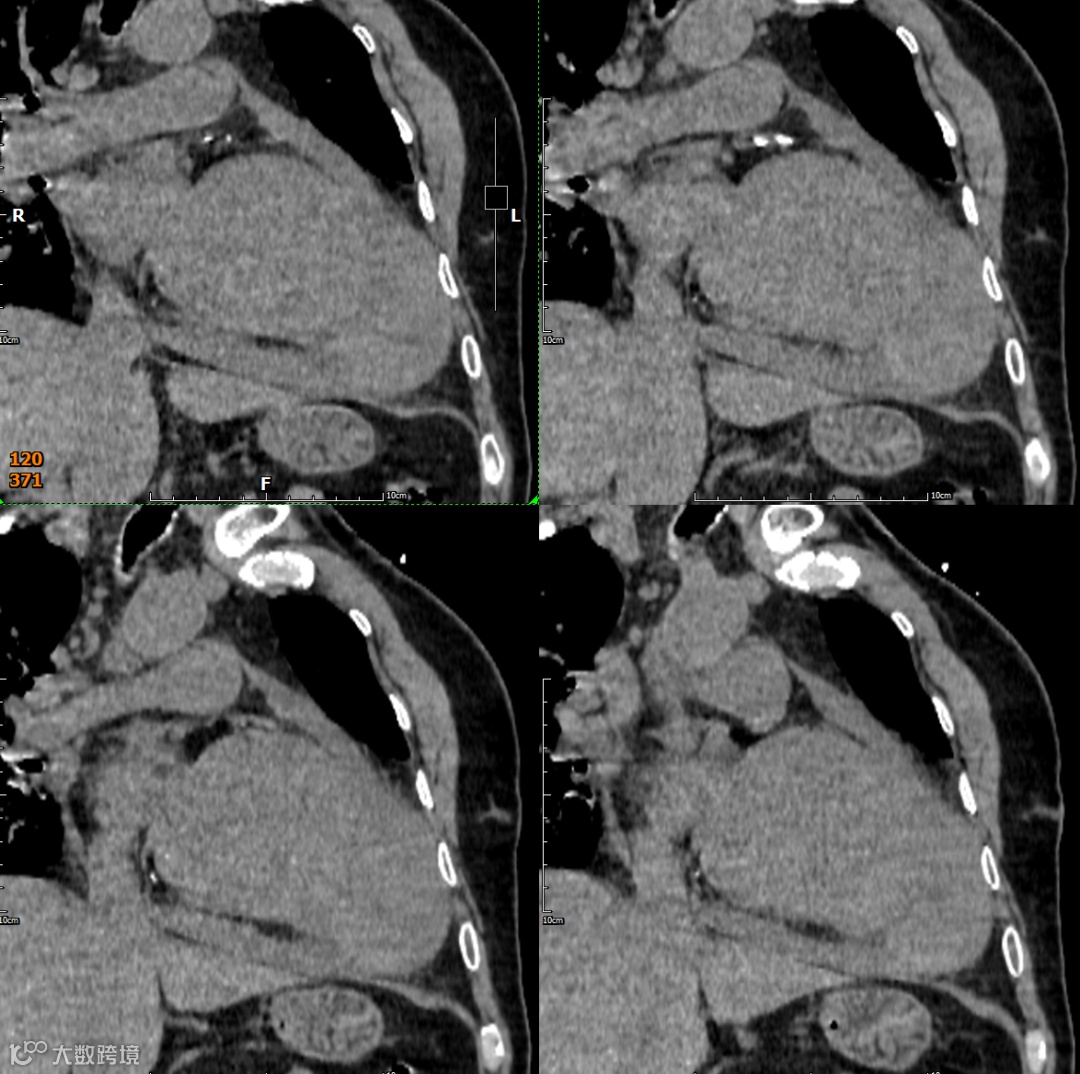

影像学检查

形态与位置:与左心室腔相邻的囊状、球状或葫芦状对比剂充盈腔。特征性的窄瘤颈是其关键。位置常在心包反折附近(下壁、后壁、侧壁)。

瘤壁:菲薄,无心肌密度!主要由心包(可能钙化)和血栓(不强化或延迟强化)构成。

瘤颈:清晰可见的、狭窄的开口(如瓶颈状)将假性瘤腔与左心室腔相连。破口处心室壁中断是直接征象。

腔内:可见对比剂充盈,内常有血栓(充盈缺损)。

心包:局部心包增厚、粘连、积液常见。瘤体常部分嵌入心包内。

多平面重建(MPR)与三维重建(3D): 对于清晰显示瘤颈的形态、大小、位置以及与左心室壁的关系至关重要。